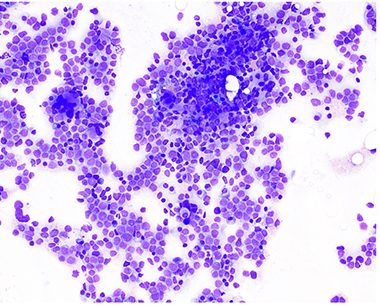

Bone Marrow Biopsy:

Increased blasts and increase promonocytes consistent with AMML. Monocytosis also noted.

Post Consolidation Morphology: 8-10% blasts/promonocyte equivalents – concern for residual disease